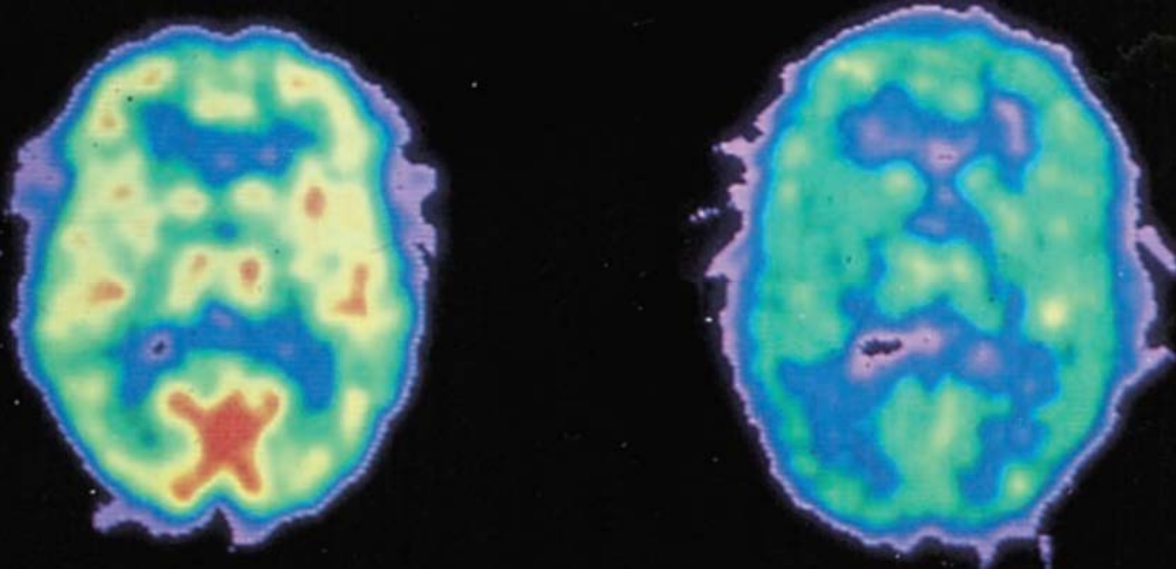

脑成像技术:

正电子发射断层扫描技术 (PET):将含有正电子的葡萄糖注射至人体静脉,葡萄糖进入大脑后,正电子与脑中负电子湮灭,发射伽马射线,PET 通过测量伽马射线强度,推测在完成各种任务时大脑中葡萄糖消耗量,从而推测大脑各脑区的功能

- 不同的认知任务引起不同脑区的活动